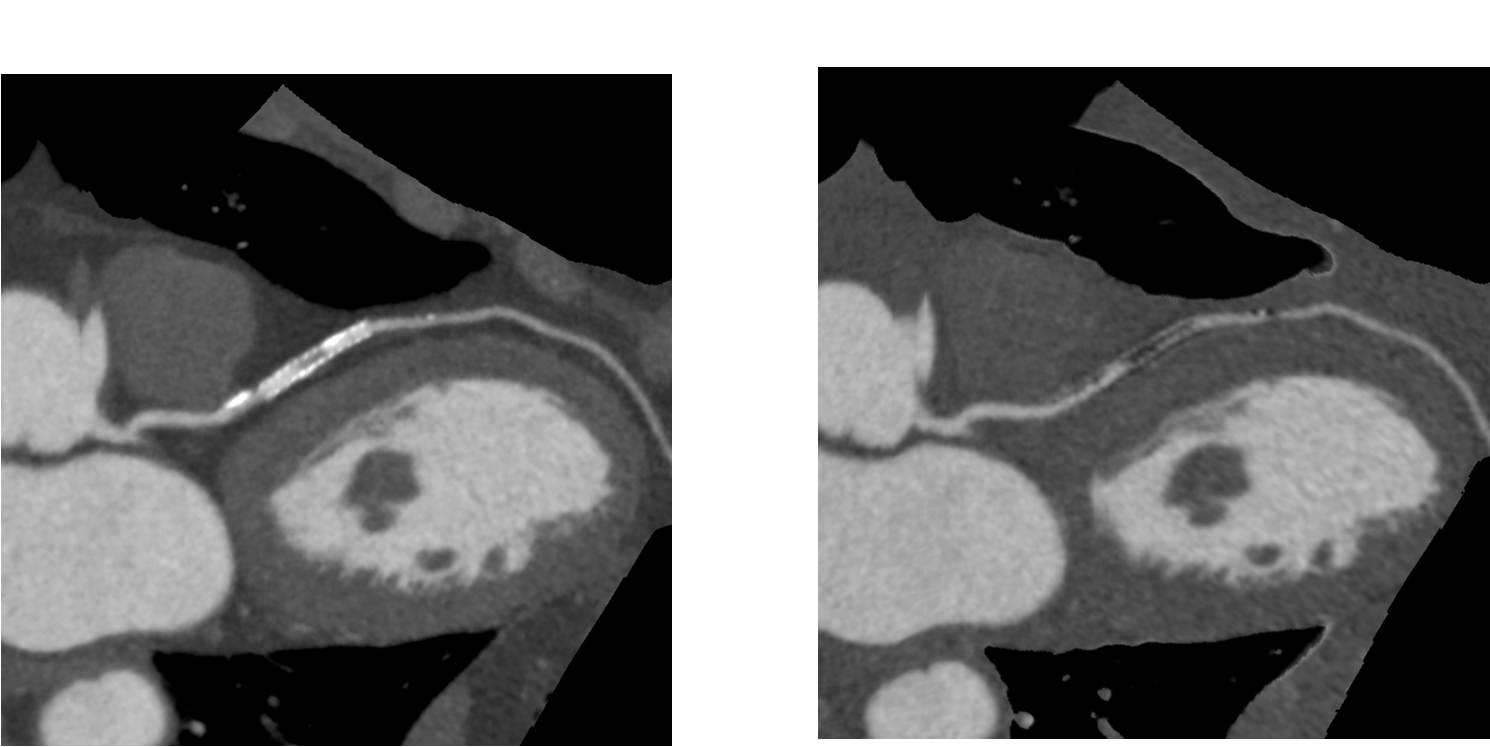

病例四 PCI后復(fù)查,前降支支架內(nèi)再狹窄。

冠脈減影前 冠脈減影后

病例五 高鈣化積分冠脈檢查